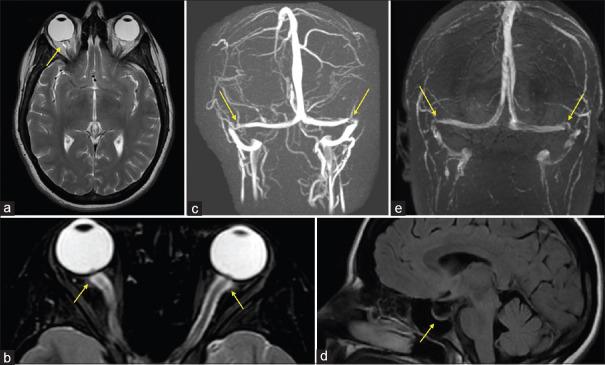

Idiopathic intracranial hypertension (IIH) primarrily affects obese women of childbearing years and is commonly associated with headaches, pulsatile tinnitus, and vision changes. Though most patients have a "benign" course, it can lead to significant morbidity, including blindness. The treatment approach is based on severity of visual impact and includes weight loss, intracranial pressure lowering medications, and sometimes surgery, such as spinal fluid diversion, optic nerve sheath fenestration, or venous sinus stenting. More studies are needed to determine when surgery is most appropriate and which surgical procedure provides maximal benefit with the least risk.

特发性颅内高压(IIH)主要影响育龄肥胖女性,通常伴有头痛、搏动性耳鸣和视力变化。尽管大多数患者病程“良性”,但它可导致严重的发病情况,包括失明。治疗方法基于视觉影响的严重程度,包括减重、降低颅内压的药物,有时还包括手术,如脑脊液分流、视神经鞘开窗或静脉窦支架置入术。需要更多研究来确定何时手术最为合适,以及哪种手术方法能以最小风险带来最大益处。